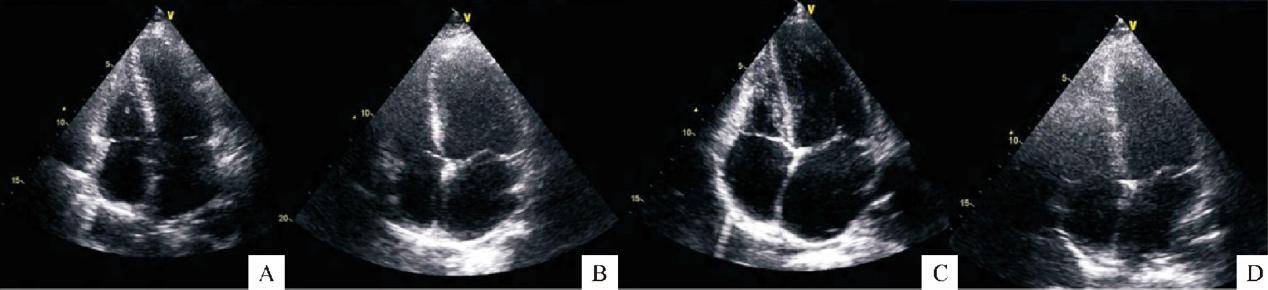

不同类型妊娠期高血压疾病的母体心脏形态学变化(A:轻度先兆子痫组;B:重度先兆子痫态组;C:慢性高血压组;D:妊娠期高血